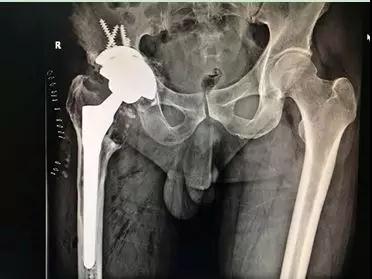

術(shù)后X線:骨小梁填充塊重建髖臼骨缺損

通過術(shù)后X線可以看出,患者假體安放位置良好,肢體長度恢復(fù),手術(shù)成功。目前該患者恢復(fù)良好,術(shù)后第二天已經(jīng)可在助行器保護(hù)下下床行走。